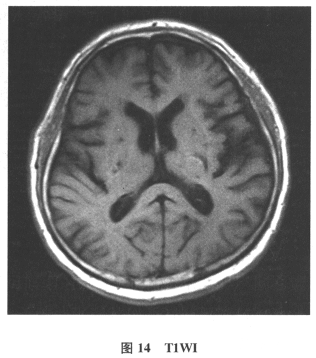

[单选题]患者男,61岁。因“发作性头晕2年,加重伴记忆力下降、走路不稳3月余”就诊。查体:BP140/70mmHg;意识清楚,构音障碍,近期记忆力及远期记忆力

[多选题]患者男,61岁。因“发作性头晕2年,加重伴记忆力下降、走路不稳3月余”就诊。查体:BP140/70mmHg;意识清楚,构音障碍,近期记忆力及远期记忆力